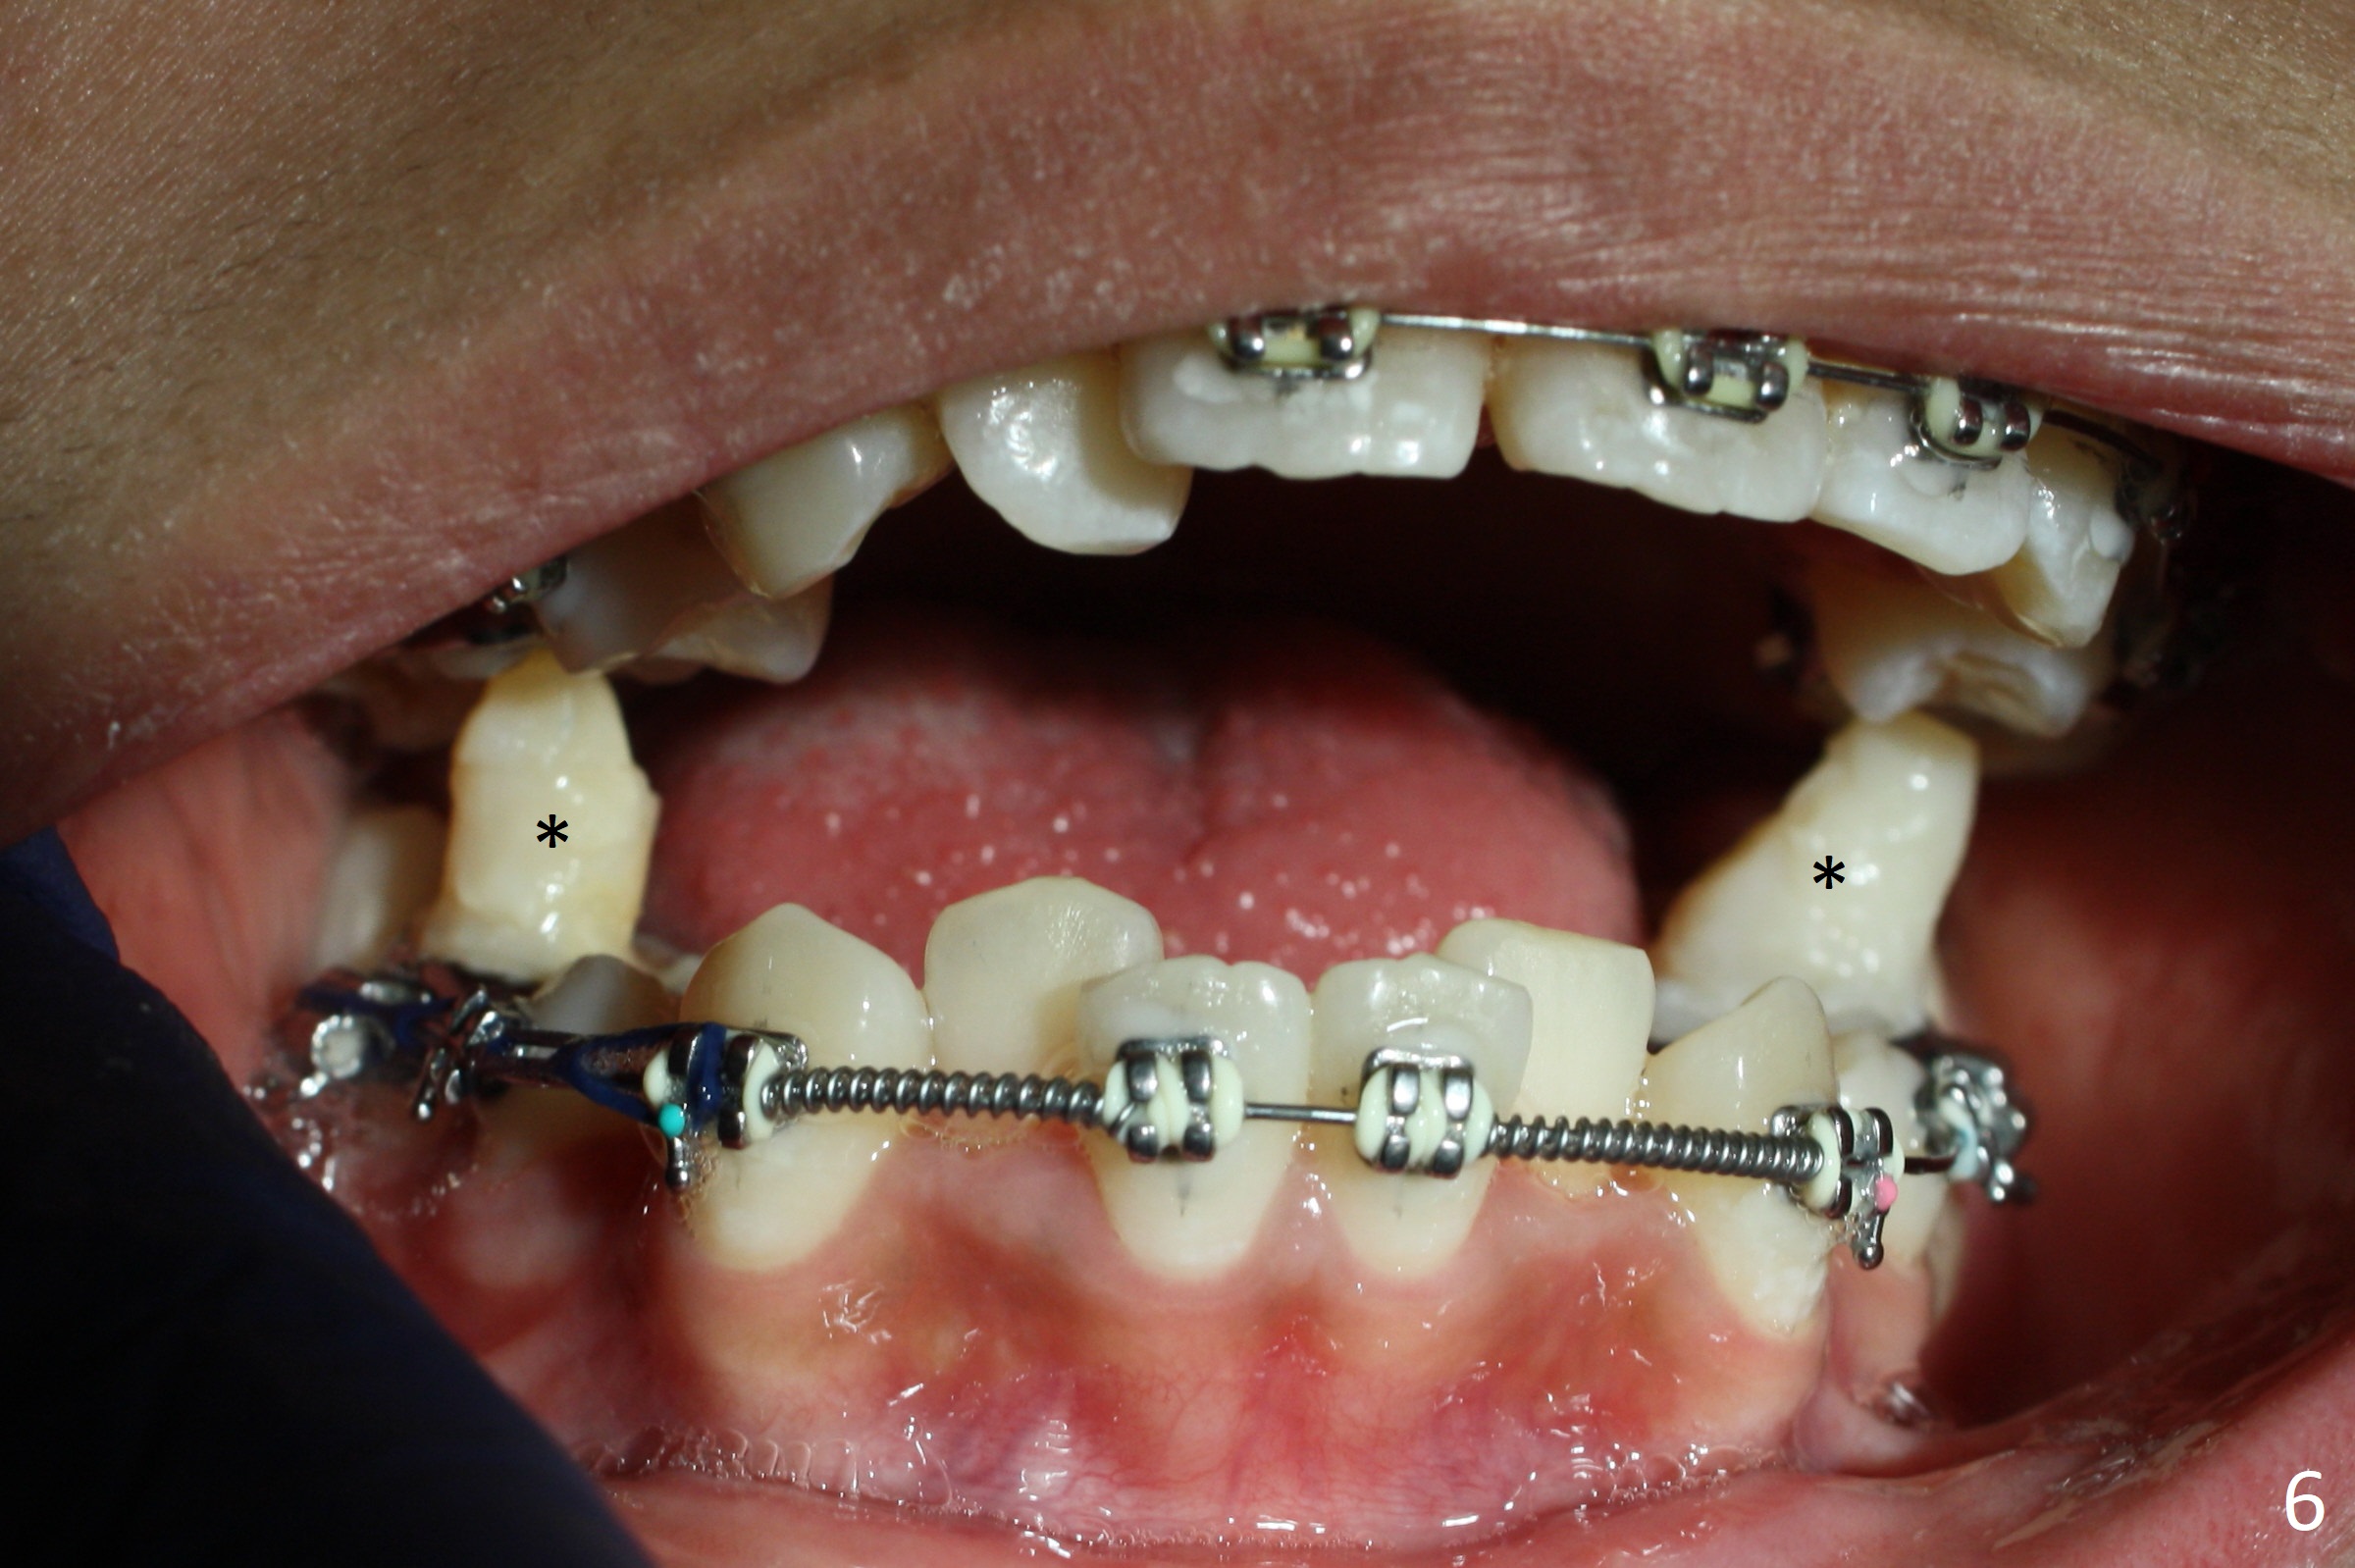

A 17-year-old woman has protrusive lips (Fig.1,2). Due to severe crowding (Fig.3-5), four of the 1st bicuspids are extracted prior to separator placement. It appears that spaces are easier to open up with extraction first. Choose 2nd molar bands with lingual cleats so that 2nd molar cross bite will be corrected immediately post banding (Fig.4,5). Place composite in the occlusal surface of the 1st molars for occlusal separation. Because of severe rotation of UR2, do not place bracket. The same can be applied to L2s. Place power chains x 4 between L3 and 6. The same mechanic will be applied to the right side when R5s are buccalized. Occlusal composite needs to be built up high and several times because of frequent wear, fracturing or detachment (Fig.6 * (1.5 months post banding)).

Three months post banding, the cross bite at 7s is corrected; with 7s' supraeruption and 6s' infraocclusion (because of occlusal composite (just removed), Fig.7,8), anterior open bite occur. Next visit place brackets in L7s with flexible wire. While 2 mechanisms are applied to gain more space for LR2 (Fig.9 *, ^), a special mechanism is utilized to correct LL2 cross bite (space gained). If the space for UR2 (Fig.10) is insufficient next appointment, what should we do? Otherwise, what should be done?